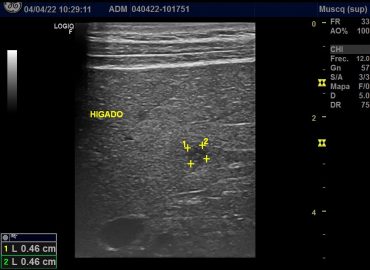

Paciente sexo masculino de 79 años, con antecedentes de HTA y diverticulosis , ingresa por presentar cuadro de lipotimia. Al […]